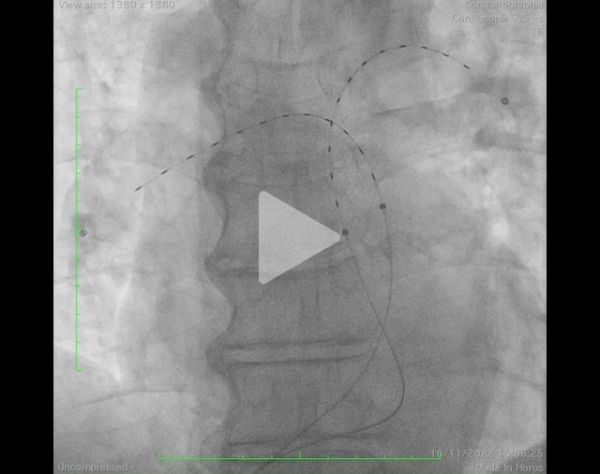

Parallèlement, un 2e dispositif percutané est disponible en France, il s’agit du système EKOS (Figure 11). Placé au niveau du thrombus dans les branches de l’artère pulmonaire, il associe la diffusion locale d’ultrasons pour faciliter la dissolution des ponts de fibrine et donc du thrombus et d’un thrombolytique à faible dose sur une durée prolongée de 12h pour réduire le risque hémorragique.

Figure 11 : dispositif EKOS - Thrombolyse in situ

Vidéo 9 : cathéters EKOS mis en place de manière bilatérale

- Cathéters 6F introduits par voie veineuse fémorale, jugulaire ou brachiale échoguidée

- Infusion ACTILYSE (dose divisée par 4 à 5 par rapport à la thrombolyse systémique) sur 12h avec émission d’impulsions ultrasonores

- Angiographie illustrant les cathéters mis en place au niveau des 2 branches de l’artère pulmonaire (Vidéo 9)